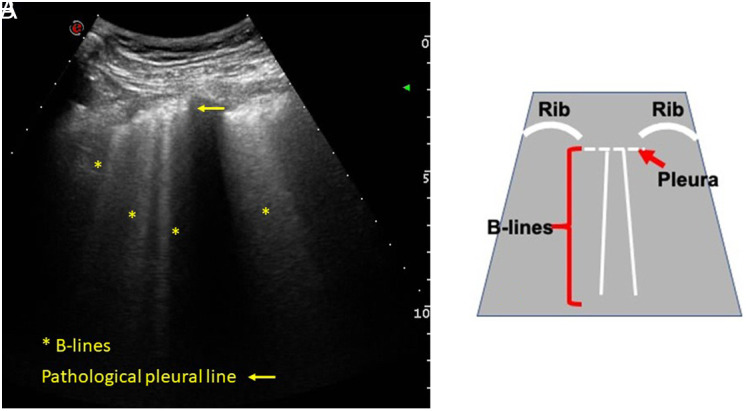

The interpretation of lung ultrasound is the result of the analysis of artifacts rather than exact representations of anatomical structures, which appear when changes in the physical properties of the lung occur. Its application to the study of interstitial lung disease (ILD) associated with autoimmune diseases has aroused great interest in the last 10 years, as evidenced by a growing number of publications studying its usefulness in the diagnostic process, as a prognostic marker and as an aid in monitoring of patients. The main elements in lung ultrasound interpretation in ILD are the B lines and the changes in the pleural line. B lines are vertical artifacts that are generated when there is a partial decrease in the air content of the lung parenchyma and/or the volume of the interstitial area expands. Pleural line alterations that can be seen are irregularities, thickening, fragmentation, or subpleural nodules. Both the B lines and the changes in the pleural line have shown a significant positive correlation with the evidence on chest computed tomography [high resolution computed tomography (HRCT)] of ILD associated with autoimmune diseases, with sensitivity and negative predictive values of up to 100%. These results, together with the safety, accessibility, and low cost of lung ultrasound, support this imaging technique as a promising screening method for optimizing the indication for HRCT. The role of lung ultrasound regarding sensitivity to change needs further investigation with multicenter prospective studies.